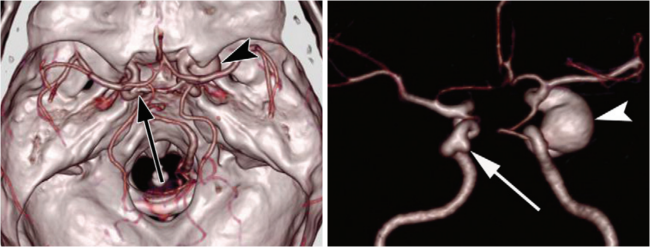

病例三 女,51歲, 近一年經(jīng)常性不明原因胸痛

一次掃描、一次打藥70ml,冠脈+全腹CTA掃描,可見(jiàn)冠脈血管多發(fā)斑塊,腹部血管CTA未見(jiàn)異常。

該檢查使用640層寬體探測(cè)器CT160排螺旋掃描技術(shù),實(shí)現(xiàn)了全身大范圍CTA檢查以及胸痛三聯(lián)征一站式檢查,僅需一次藥,在一次掃描中實(shí)現(xiàn)采集。

病例四 PCI后復(fù)查,前降支支架內(nèi)再狹窄。

冠脈減影前 冠脈減影后

病例五 高鈣化積分冠脈檢查